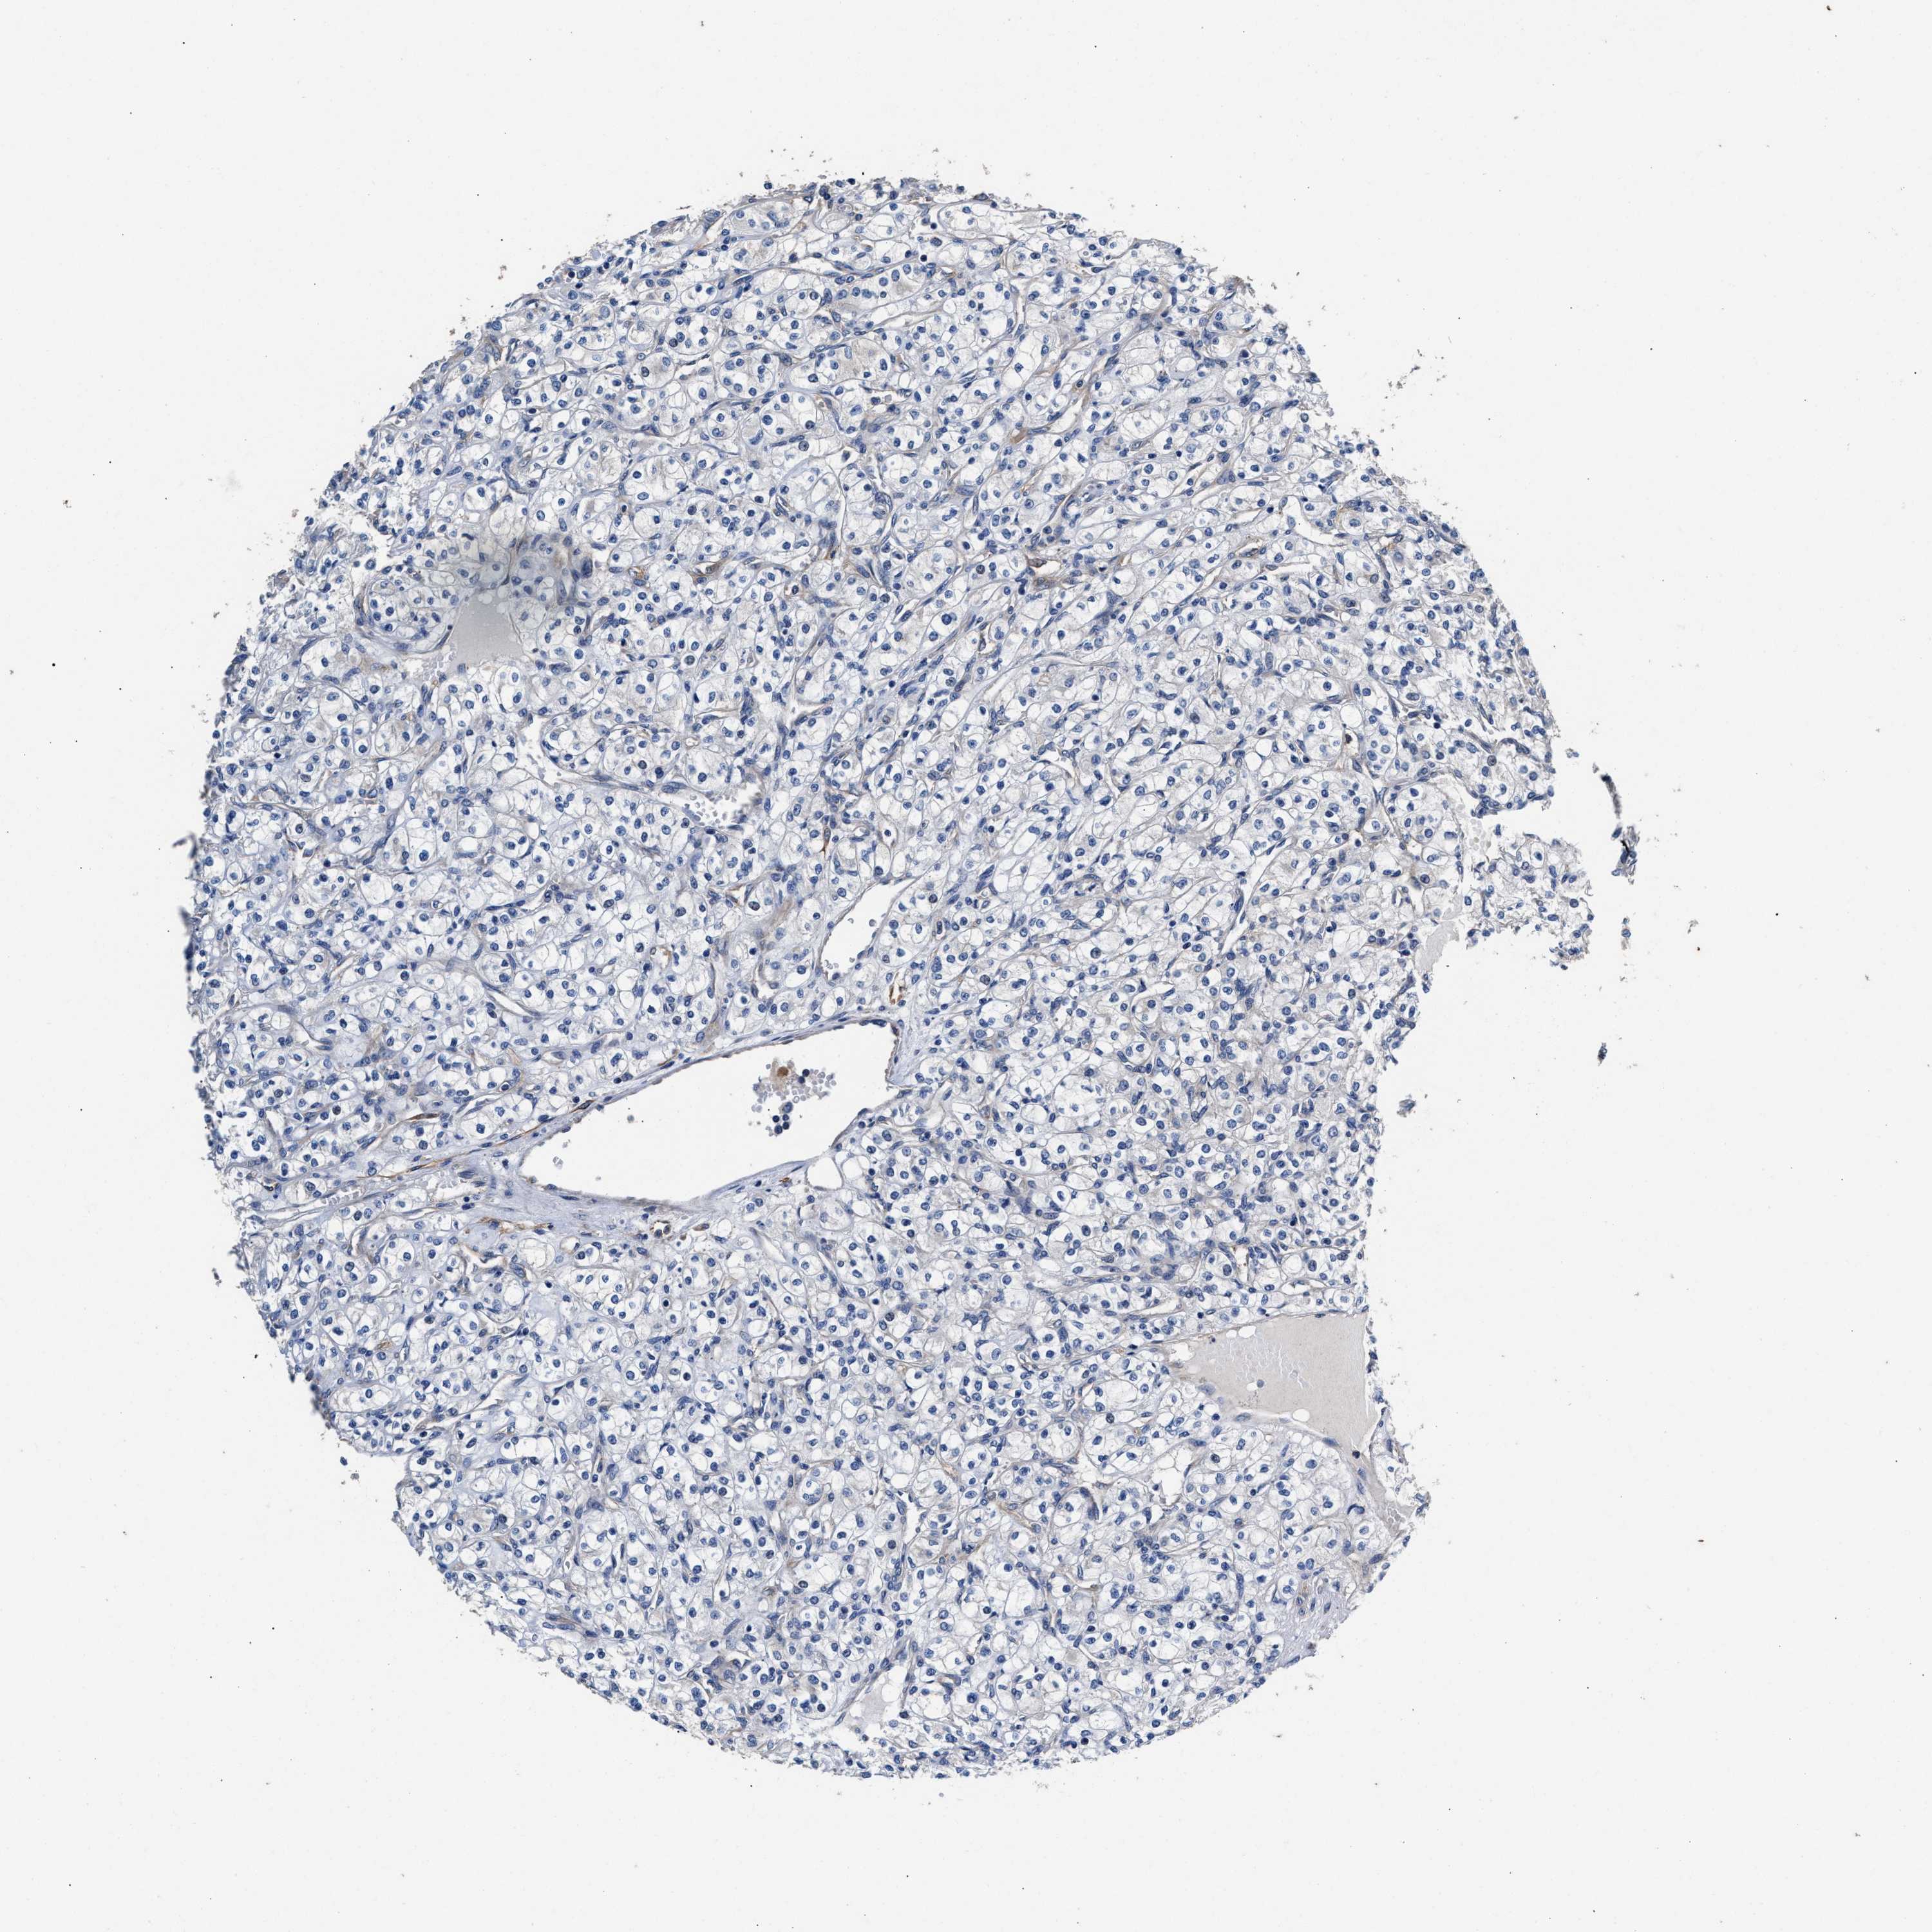

CANCER RENAL CANCER Show tissue menu

KICH TCGA KIRC TCGA KIRC VALIDATION KIRP TCGA PROTEIN RCC CPTAC PROTEIN EXPRESSION

Renal cancer

Kidney renal papillary cell carcinoma